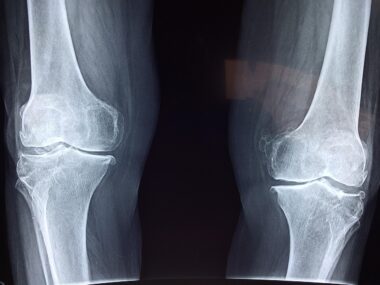

Collagen plays a crucial role in maintaining the integrity and health of cartilage, the tissue that cushions joints. As we age, collagen production declines, leading to joint pain and stiffness. Joint health supplements containing collagen have gained popularity due to their potential benefits in alleviating these issues. Collagen peptides, broken down for better absorption, support the regeneration of cartilage and connective tissues, making them essential in joint health formulations. Studies show that regular intake can enhance joint comfort, flexibility, and overall mobility. Moreover, collagen supplements often include other beneficial ingredients such as glucosamine and chondroitin. Glucosamine aids in maintaining cartilage structure, while chondroitin helps attract fluid into the joint. This combination can provide a synergistic effect, improving joint health and function significantly. Targeted supplementation can be particularly beneficial for athletes and individuals engaged in strenuous physical activities. Research indicates a noticeable reduction in joint pain among those who take collagen supplements consistently. Additionally, increased collagen levels can support skin elasticity and hydration, highlighting its multifunctional properties. Understanding the science behind these benefits can help individuals make informed choices regarding joint health supplements.

Collagen and Its Benefits for Joint Health

The integration of collagen supplements into daily routines must be complemented with lifestyle practices promoting joint health. Regular physical activity strengthens muscles around joints, enhancing stability and mitigating discomfort. Low-impact exercises, such as swimming and cycling, have shown to benefit joint health, while stretching enhances flexibility. Furthermore, maintaining a healthy weight reduces stress on joints, particularly weight-bearing ones like knees and hips. A balanced diet rich in fruits and vegetables, whole grains, healthy fats, and lean proteins provides essential nutrients—including vitamins C and D—for collagen synthesis. Adequate hydration is equally important; water aids joints in staying lubricated and functioning correctly. Incorporating supplements, healthy eating, and physical activity creates a holistic approach to joint health. This combination can significantly enhance the long-term effectiveness of collagen supplements leading to sustained results. Routine check-ups with a healthcare provider also ensure that any underlying health issues are addressed, further promoting joint health outcomes. Consultation will also assist in modifying supplements as required. Thus, multifaceted strategies are fundamental in achieving optimal joint health, enabling individuals to lead active and fulfilling lives.